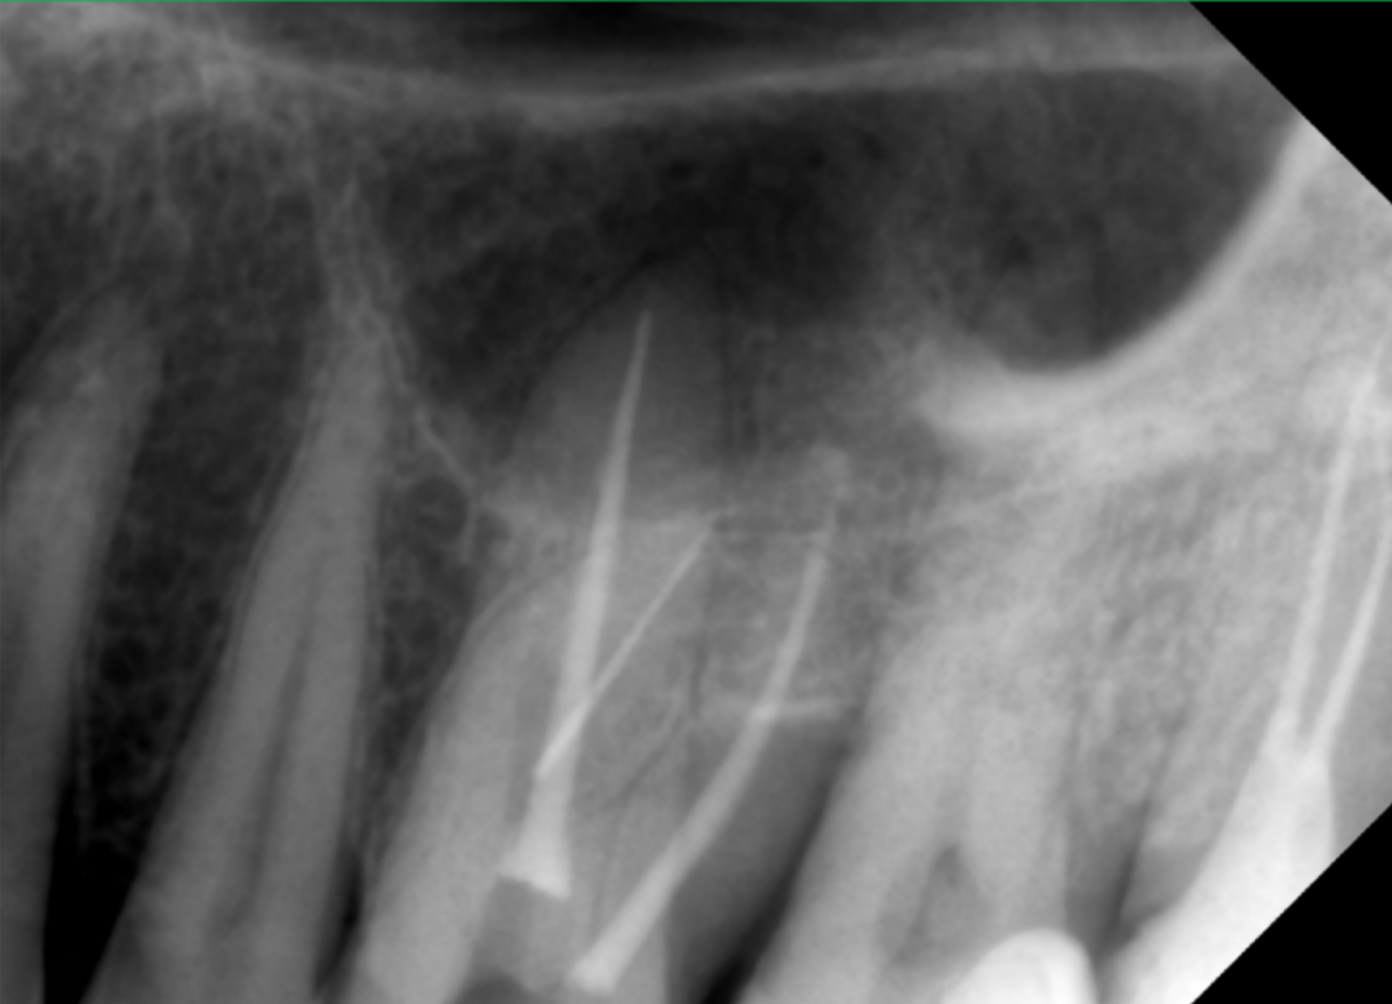

Pentru ca exista suspiciunea ca fragmentul separat se afla in contact cu sinusul maxilar si pentru ca stim ca s-a incercat indepartarea acului cu ajutorul ultrasunetelor si ne asteptam sa existe o perforatie, efectuam imagistica tridimensionala care ne confirma toate aceste lucruri(fig. 2 – sectiune CBCT).

Prezenta unui ac separat in sistemul endodontic este o situatie manageriabila dar mult complicata de existenta unei perforatii obtinute ca si consecinta a incercarii de indepartare. Depasirea foramenului apical face ca tentativa de indepartare sa prezinte risc de impingere, in cazul de fata, in sinusul maxilar.